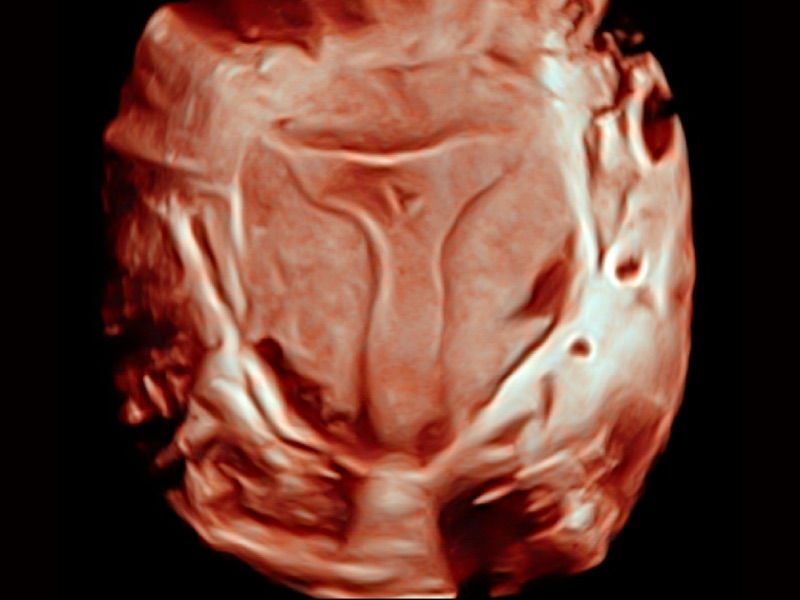

心血管应用

三维光影成像技术采用新型的渲染方式,增强边缘信息,使得轮显示清晰完整,为临床提供丰富、直观的三维结构,提供临床诊断准确性。